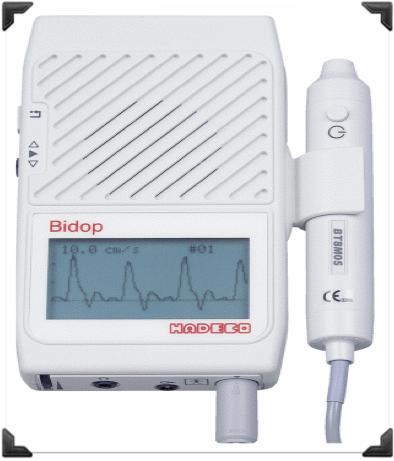

PULSOS (flujo)